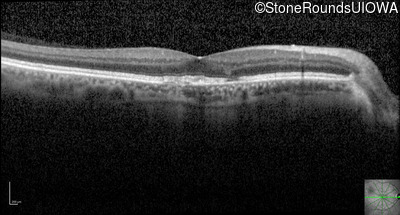

Optical Coherence Tomography - Left - 20/40 +1

Exemplar / OCT Stack